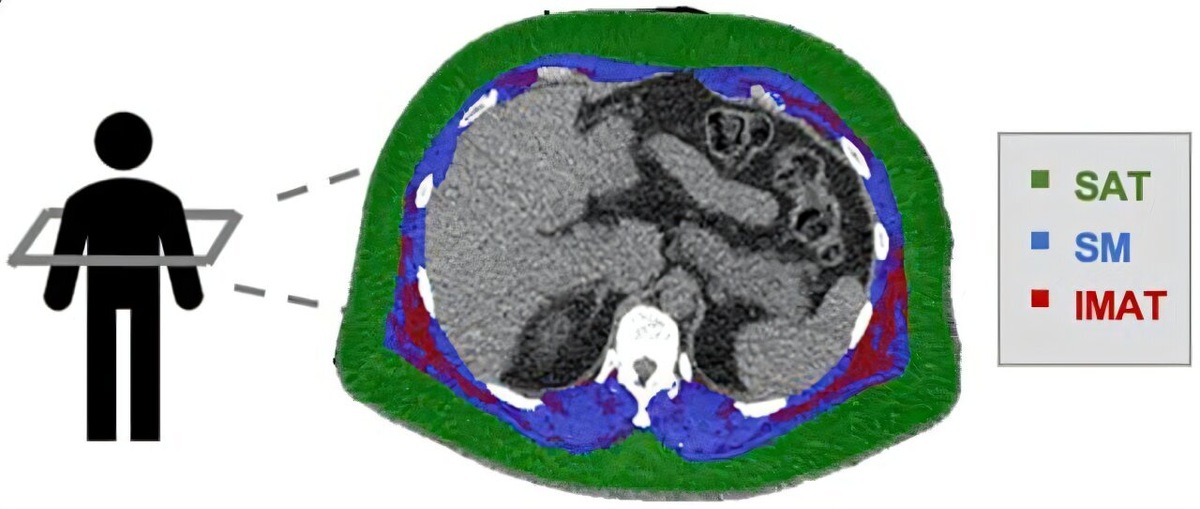

Межмышечный жир есть в большинстве мышц нашего тела. Однако количество этого жира может значительно различаться у разных людей.

Учёные рассчитали соотношение межмышечного жира к общему объёму мышц и жира. Этот показатель они назвали жировой фракцией мышц.

Люди, у которых было много межмышечного жира и были признаки коронарной микрососудистой дисфункции, были подвержены особенно высокому риску смерти, возникновения сердечного приступа и сердечной недостаточности. В то же время те, у кого было много сухой мышечной массы, имели более низкий риск. Подкожный жир при этом не увеличивал этот риск.